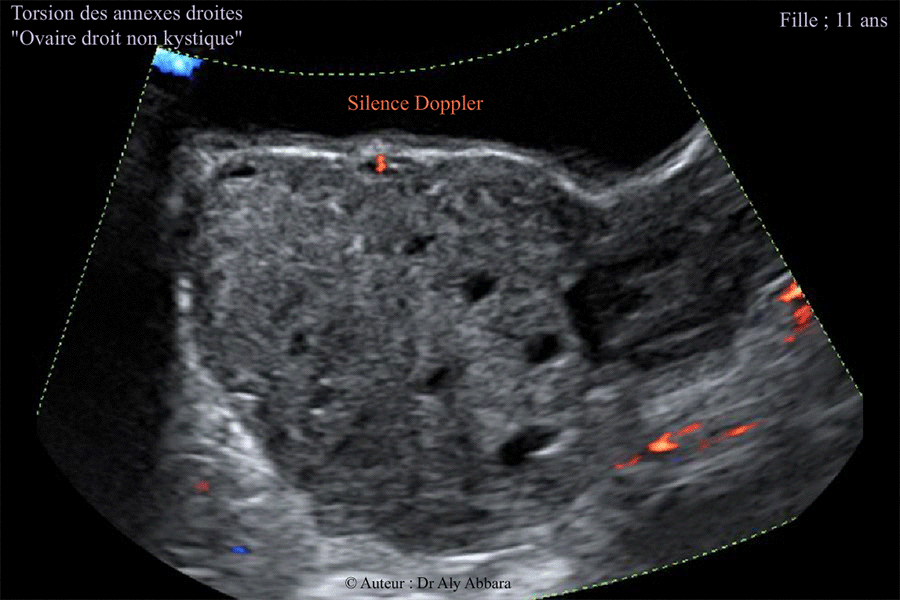

Torsion des annexes utérines droites chez une fille de 11 ans - Silence Doppler sur l'échographie

Images échographiques montrant une torsion des annexes utérines droites chez une fille de 11 ans (non encore réglée - pas de ménarche) - ovaire droit non kystique.

L'image présentée montre, grâce au Doppler-couleur, l'absence de flux sanguin au sein de l'ovaire droit tordu et ischémique (silence Doppler).

L'image montre également un ovaire droit augmenté de volume (73 cm3 contre 8 cm3 qui est le volume de l'ovaire gauche non tordu). On observe la présence des follicules antraux (de 2 à 5 mm de diamètre) dispersés au sein de cet ovaire et séparés par un stroma ovarien œdémateux et infiltré (cliniquement par le sang) et fort probablement nécrobiosé par une ischémie liée à l'obturation mécanique des vaisseaux vascularisant normalement les annexes utérines (torsion de 720° à l'inverse des aiguilles de montre : du ligament utéro-ovarien ; du ligament large et du ligament lombo-ovarien droits).

La trompe droite qui est individualisable sur une autre image est augmentée de calibre ; infiltrée et ischémique (comme l'ovaire homolatéral).

Il existe aussi un petit épanchement pelvien, péri-annexiel droit (cliniquement : liquide péritonéal sanglant d'environ 100 cc de volume).